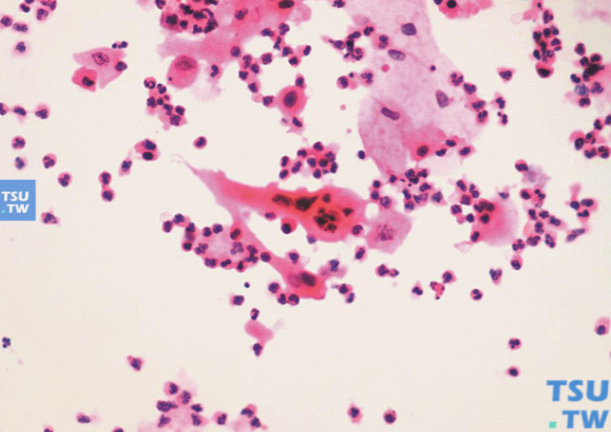

印度科学家的最新研究彻底刷新了医学界对衰老细胞的认知。这些被称为"僵尸细胞"的衰老细胞,虽然失去了正常分裂和功能,但却不会自然死亡,反而会持续分泌大量炎性因子、蛋白酶和生长因子,形成SASP(衰老相关分泌表型)毒性微环境。研究证实,这种毒性环境不仅会攻击周围健康细胞,导致皮肤胶原蛋白流失、代谢紊乱,更严重的是会为癌细胞生长和转移创造有利条件。